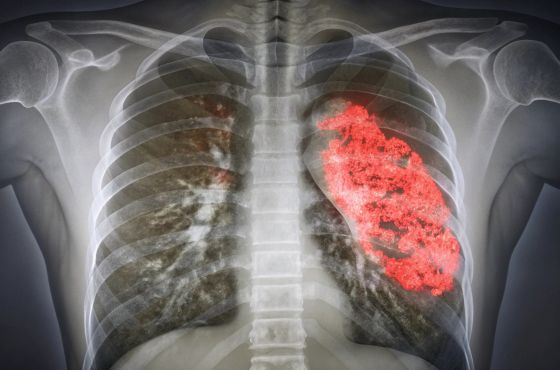

La neumonía, también llamada pulmonía, provoca inflamación en los pulmones debido a infecciones virales o bacterianas. Con equipos adecuados, como radiografías torácicas, es posible detectar la enfermedad a tiempo y tratarla con antibióticos, lo que puede reducir la mortalidad en niños menores de 2 años hasta en un 42%.